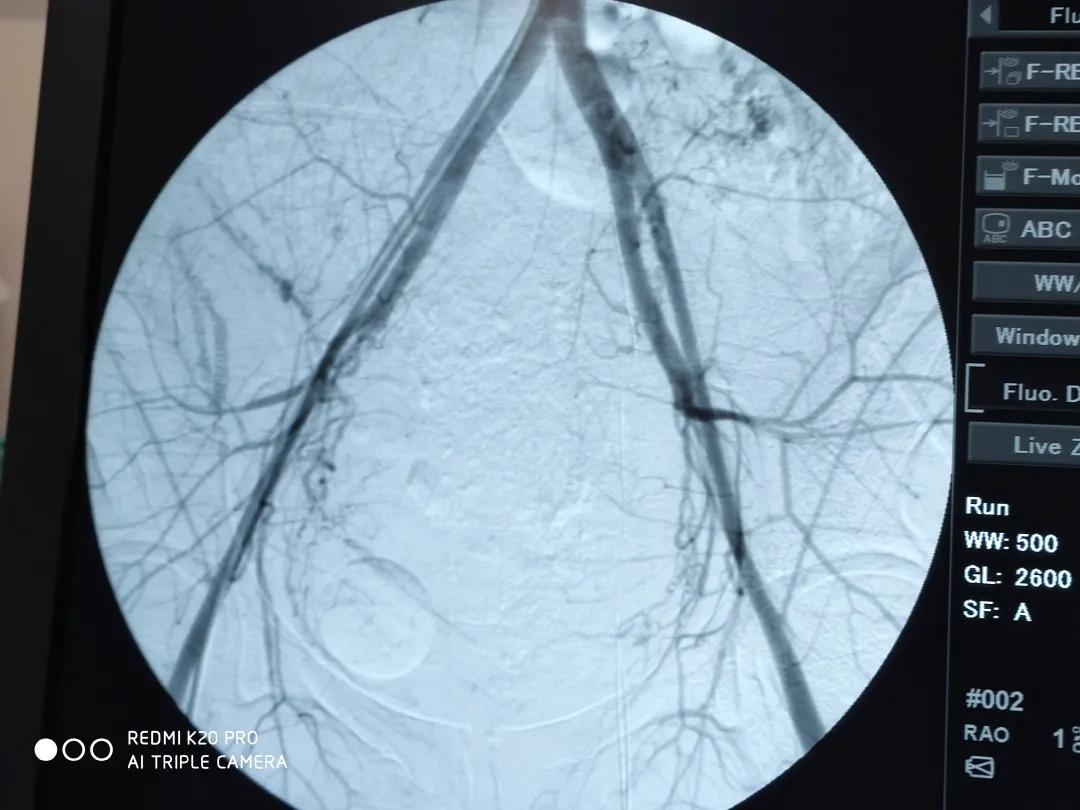

基层的医护人员一路紧急护送病人小丽(化名)来到开封市人民医院导管室。此时,在输血措施支持下病人血压已经恢复正常。但面色仍然苍白!身体下面有血液近800ml。在麻醉科丁丽主治医师、金晓烨主任带领孔豪医师、孙俪护师全力配合下。陈帅主任带领介入团队迅速消毒铺巾开始手术。考虑到病人26岁,又是第一胎,尽可能在止血的同时保留子宫的功能。所以,介入团队选择超选择子宫动脉进行栓堵。时间一分一秒地流逝,经过近2个多小时的努力。介入手术完成了,患者阴道出血减少了。